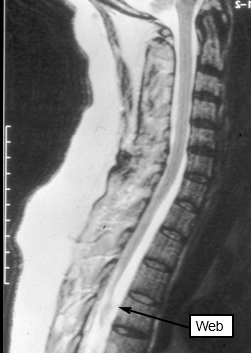

What are the causes of spinal arachnoid webs?

May be idiopathic or secondary to previous inflammatory processes caused by infection or intracranial haemorrhage